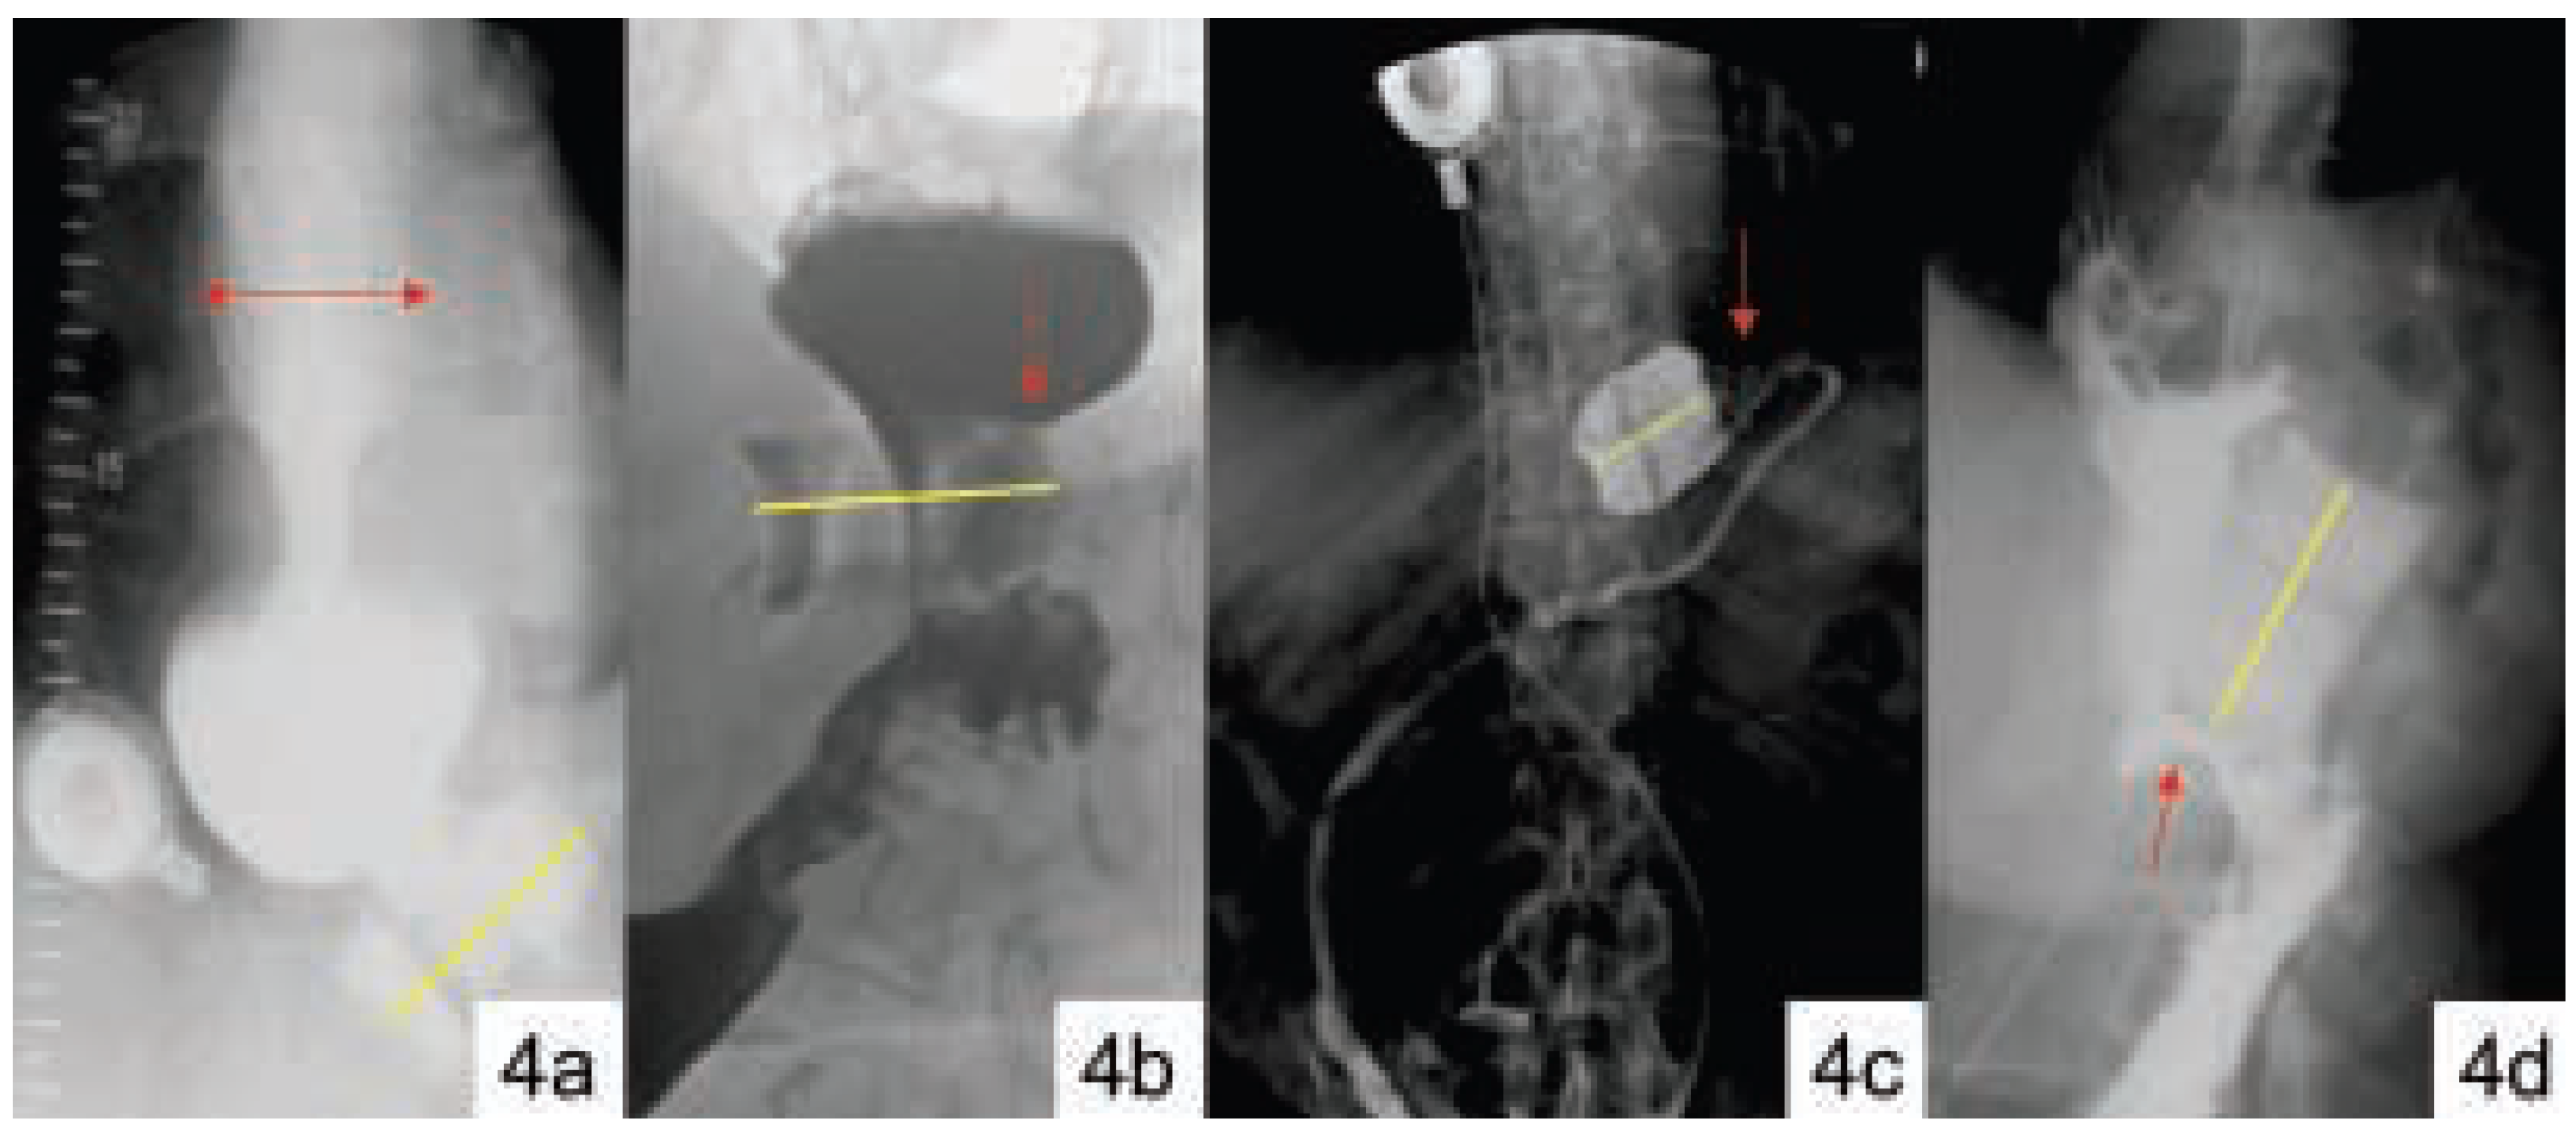

Komplikationen

Komplikationen (Tableau 3)